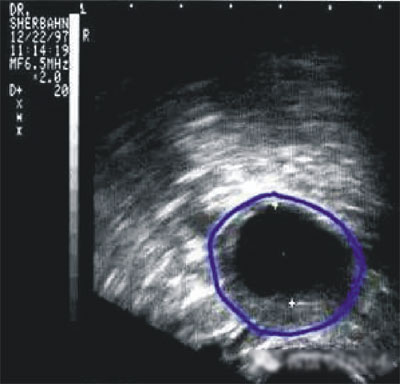

陰道B型超聲動態(tài)監(jiān)測卵泡的發(fā)育及排卵,是監(jiān)測排卵最準(zhǔn)確可靠的方法。通過陰道B超檢查可以了解子宮及雙側(cè)附件(卵巢和輸卵管)區(qū)的基本情況,測定卵巢內(nèi)的竇卵泡計數(shù),評估卵巢儲備功能,動態(tài)監(jiān)測排卵。